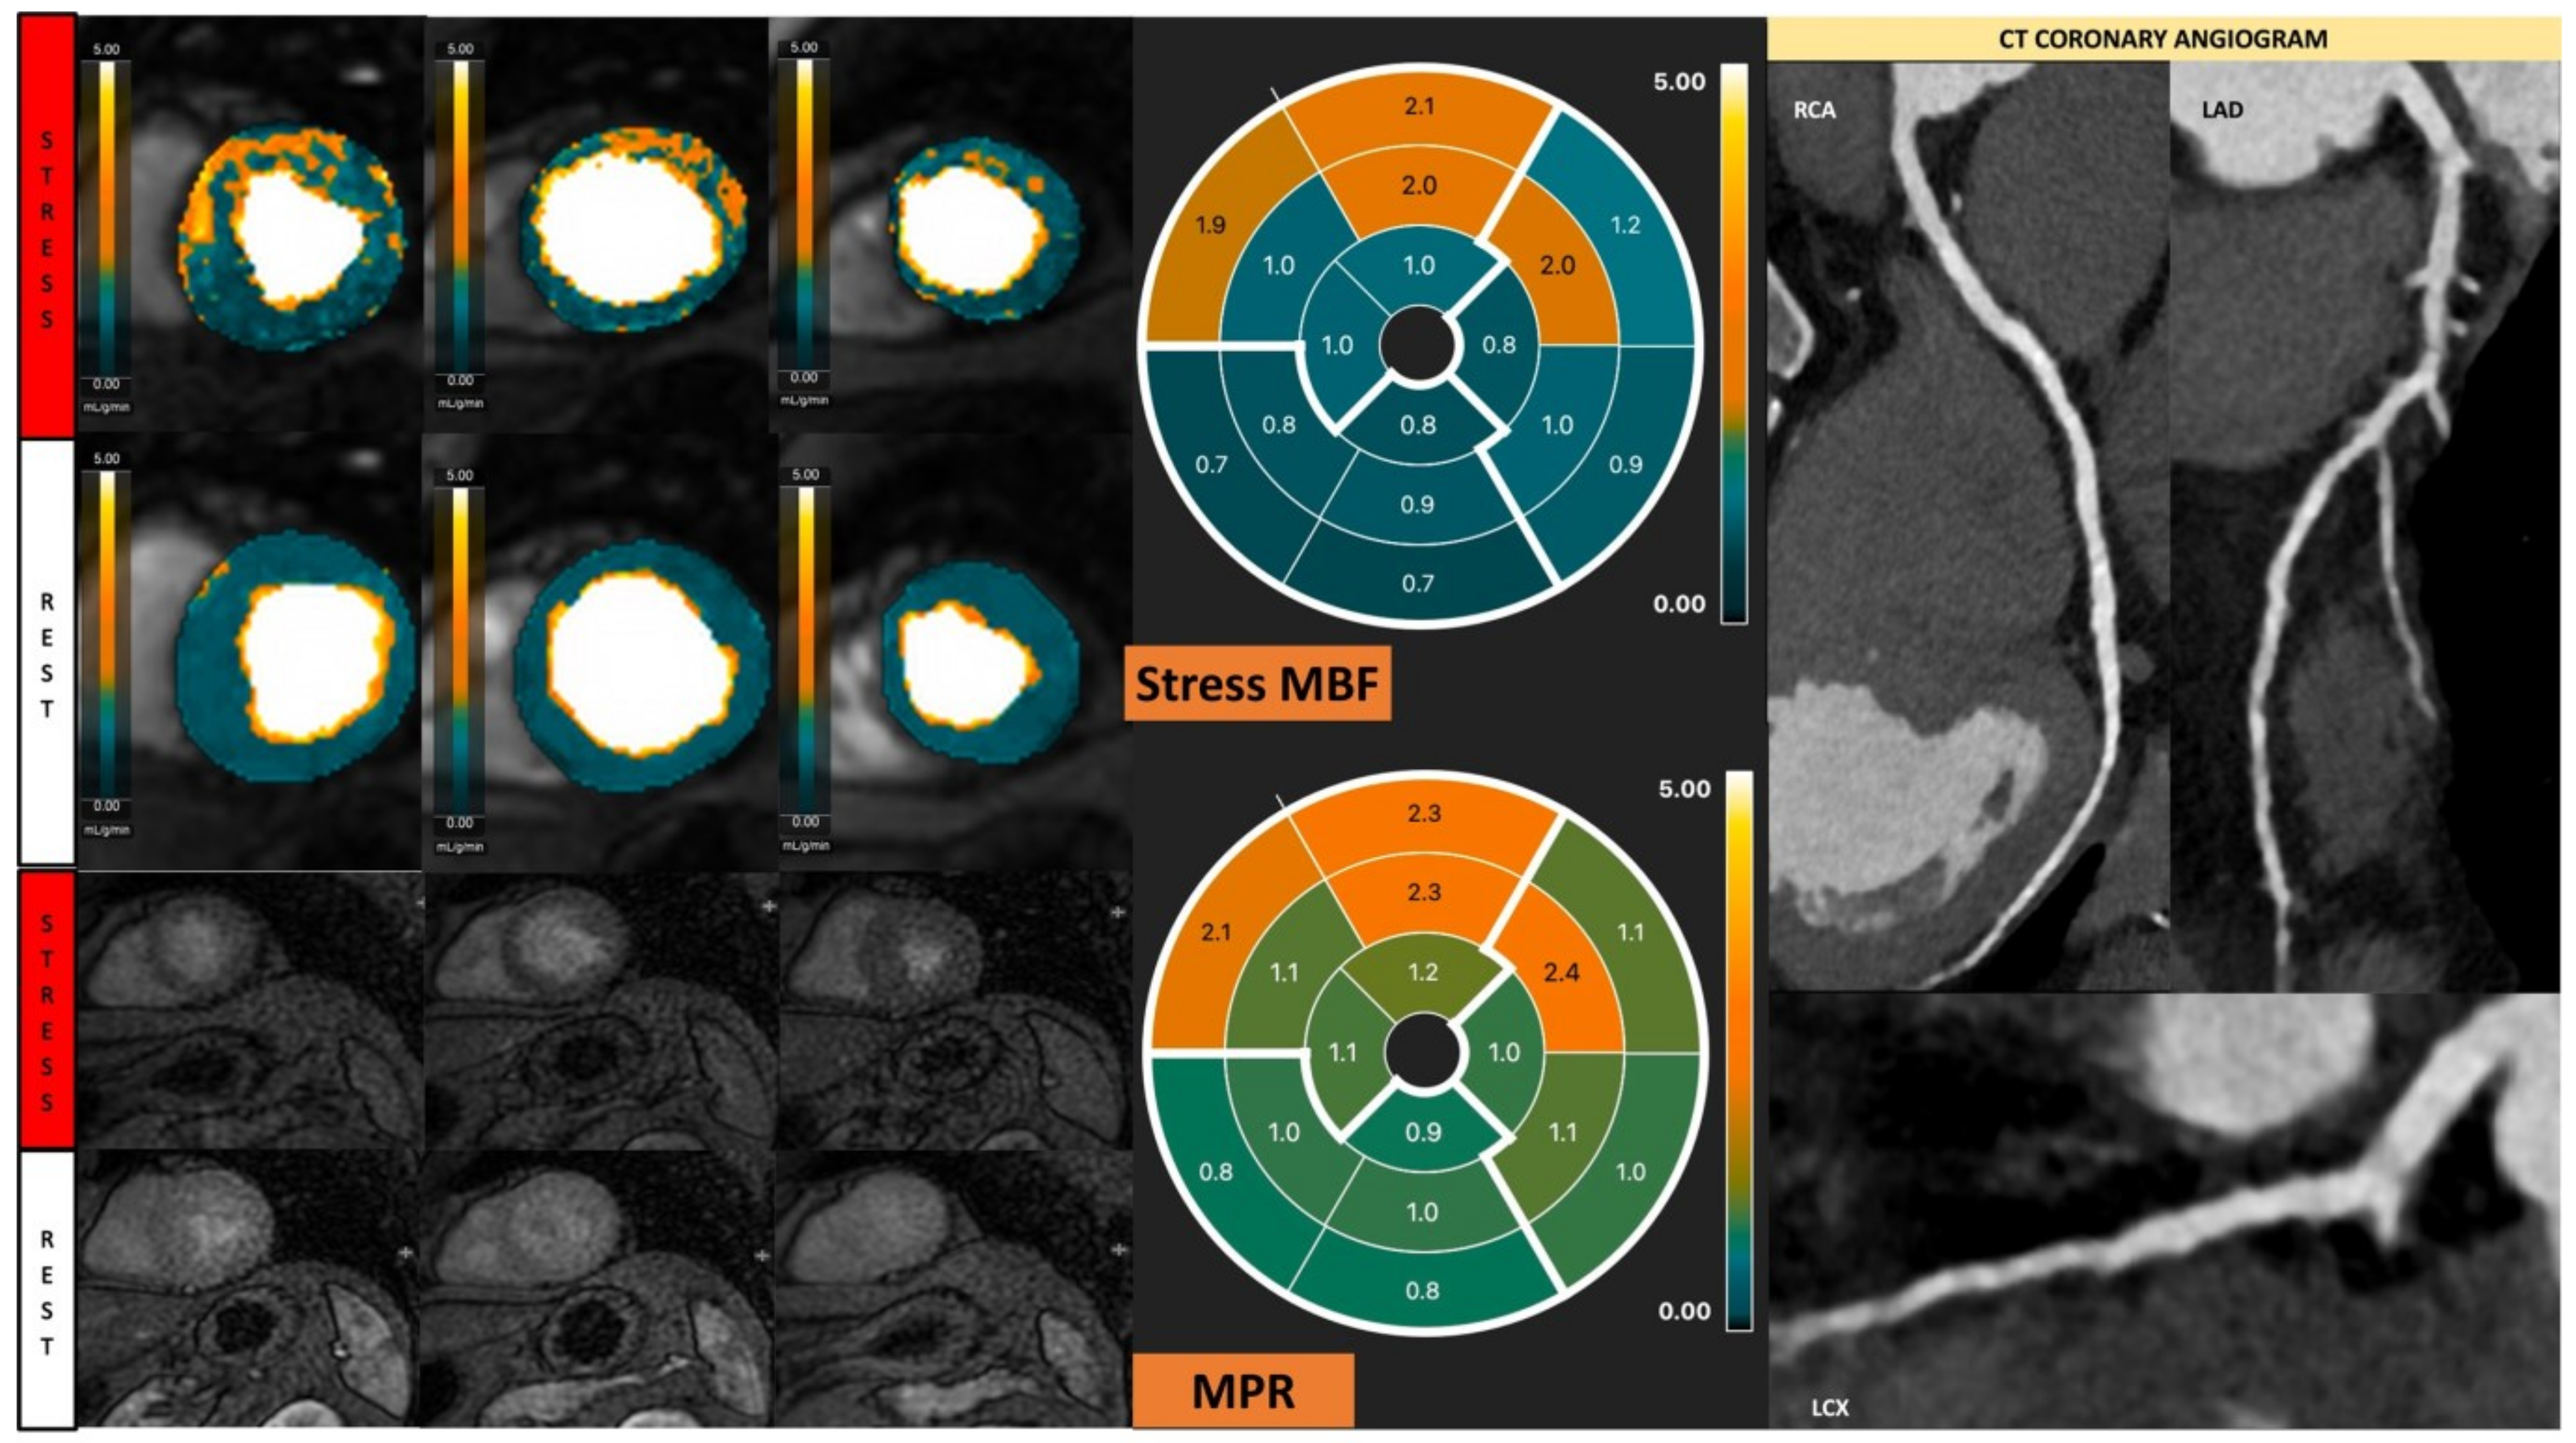

Figure 8.

Quantitative stress CMR examination of dilated cardiomyopathy. Female patient in her 60s with dilated cardiomyopathy and phospholamban genetic mutation. Patient underwent stress CMR, having presented with symptoms and signs of heart failure. Top left panel of six images shows quantitative perfusion images with reduced global myocardial blood flow (MBF) during stress. Lower left panel of stress perfusion images shows no stress-induced perfusion defect. Stress MBF and myocardial perfusion reserve bulls-eye plots objectively demonstrate this low perfusion. Coronary computed tomography multiplanar reformat images of the three main coronary arteries show no significant coronary artery disease.